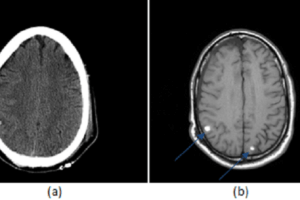

Non-penetrating head trauma

Trauma is the sixth leading cause of death world wide. Non-penetrating head trauma is the most common form of trauma and involves forces that impact but do not penetrate the parenchyma. Motor... Read more »